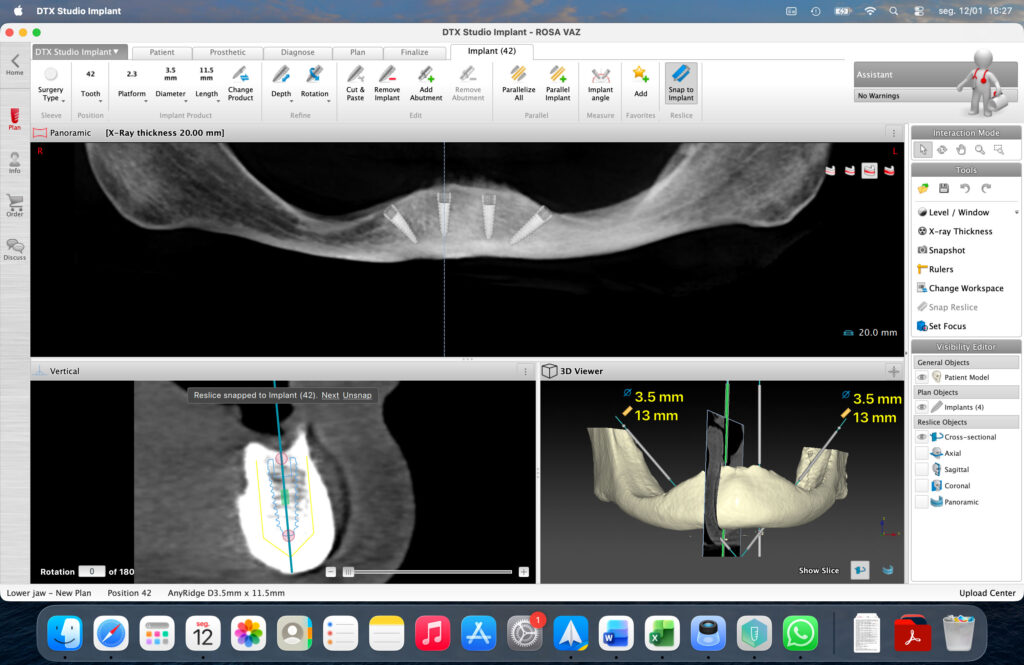

Case presentation: A 75-year-old female patient presented with a fully edentulous maxilla affected by Kelly syndrome, advanced maxillary sinus pneumatization, and reduced bone height and width. The mandible showed an anteriorly positioned inferior alveolar nerve in the premolar regions. Full-arch rehabilitation was performed using an All-on-Six protocol in the maxilla with six straight MegaGen BlueDiamond® implants (Ø 3.3, 3.7, and 4.1 mm) placed using a palatal approach and osseodensification with Densah® burs. The mandible was rehabilitated with an All-on-4 protocol using MegaGen AnyRidge® implants (Ø 3.5 and 4.0 mm).

- Protocol: All-on-4

- Implant System: MegaGen AnyRidge®

- Implant Diameters: Ø 3.5 mm and Ø 4.0 mm

- Implant Configuration: Four implants placed anterior to the mental foramina

A comprehensive diagnostic work-up was performed, including panoramic radiography and cone-beam computed tomography (CBCT), to assess bone volume, sinus pneumatization, ridge morphology, and the position of critical anatomical structures.

The maxillary arch presented severe horizontal and vertical bone resorption, advanced sinus pneumatization, and a palatal shift of the residual ridge, consistent with Kelly syndrome. In the mandible, CBCT analysis revealed an anteriorly positioned inferior alveolar nerve in the premolar regions, limiting the safe placement of implants in these areas.

Based on these findings, a full-arch rehabilitation was planned using a fixed implantsupported prosthesis, with an All-on-Six protocol in the maxilla and an All-on-4 protocol in the mandible. Implant diameters and lengths were selected to maximize primary stability while respecting the available bone volume and avoiding the need for extensive grafting procedures.